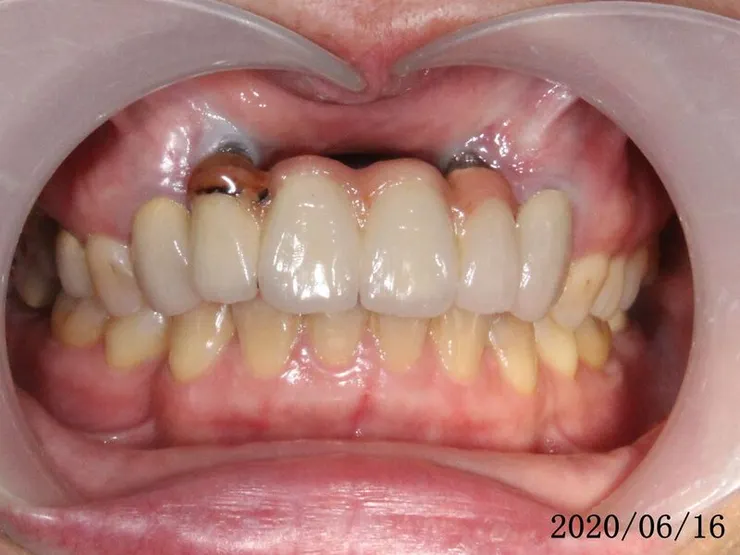

請注意開始是2017,花了一年多,才終於走到裝正式假牙

再經過一年,假牙看起來更自然了,當初剛裝假牙時的牙齦,病人自己說大概一個多月就自動長好恢復了

正中門牙的黑三角,無解,那是成人重做門牙或矯正常見的問題,因為已不像年輕人的牙齦那麼有再生活力與適應力,所以很多牙醫師都喜歡做連在一起的假牙,解決黑三角的問題(可參考她最上面的原始假牙),可這是對醫師方便、好,對病人的健康並不好。

我的預設值本來就是單顆獨立分開的假牙(只要條件允許)。

這是2021的,一樣自然好看

她有用音波牙刷潔牙,保持牙周健康,牙齦更飽滿了,假牙看起來更自然(可以跟她其他的金屬瓷牙比較)